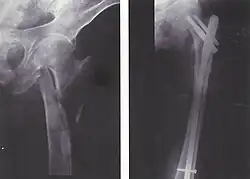

Schematische Darstellung eines Marknagels bei einer Oberschenkel-Fraktur

Der heutige Stand der Technik sind Marknägel aus weitgehend inertem Titan. Diese Implantate bieten die Möglichkeit einer statischen oder dynamischen Verriegelung sowie einer Kompression auf den Frakturspalt. Versorgt werden geschlossene und einfach offene Frakturen der großen Röhrenknochen (Oberschenkel (Femur), Schienbein (Tibia), Oberarmknochen (Humerus) ). Andere Versorgungen stellen Außenseiteranwendungen in Spezialfällen dar. Für gelenknahe Frakturen an oben genannten Knochen gibt es eine Reihe von Spezialimplantaten mit besonderen Eigenschaften wie z. B. den Gammanagel, proximalen Humerusnagel oder distalen Femurnagel. Die Implantate sind auf den Zielknochen anatomisch vorgeformt und in verschiedenen Dicken und Längen erhältlich.